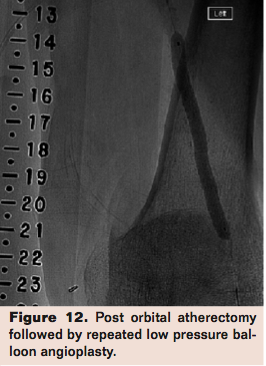

Compliance 360 was the same design but in 50 patients with FP lesions. Adjunctive stenting was needed in 8% in the OA arm vs 84% in the PTA arm (P<.0001). Mean maximum balloon pressure (a measure of lesion compliance) in the OA arm was 3.9 atm vs 9.1 atm in the PTA arm (P<.0001). Freedom from TLR (including acute adjunctive stenting) or restenosis at 6 months was met in 72.7% of the OA arm and 8.3% of the PTA arm (P<.0001). By 12 months, restenosis or repeat TLR occurred in 5 of 21 in the PTA arm (4 in-stent) and 5 of 20 in the OA arm (P=NS).18 The CONFIRM registry series was designed to evaluate OA in PAD of lower extremities, as well as to optimize the OA technique. It studied a total of 3,135 patients originally enrolled in either CONFIRM I (Diamondback 360); CONFIRM II (Predator 360); and CONFIRM III (Diamondback 360, Predator 360, and Stealth 360). Eighty-one percent of lesions had moderate to severe calcification with an average preprocedural stenosis of 88% as adjudicated by the treating physician. Treatment with OA reduced stenosis from 88% to 35%. Final residual stenosis after adjunctive treatment (low-pressure PTA at a mean of 5.5 to 5.8 atm) averaged 10%. The key take-home points from the series were that shorter spin times and the use of smaller crown sizes significantly decreased procedural complications including slow flow, vessel closure, and spasm.19 This illustrates the concept that plaque modification provides better outcomes than plaque debulking. As evidenced in the studies, OA is effective in the treatment of calcified lesions in the FP segment as well as below the knee. As a limitation, these studies share the lack of core lab adjudication of angiographic data. In summary, compared to PTA alone, OA with low pressure PTA leads to better luminal gain by improving lesion compliance with less need for adjunctive stenting when treating calcified FP lesions. Patency at 12 months is comparable to PTA with a provisional stent strategy. Occasionally, a lesion continues to show a “waist” (Figure 11) after Diamondback atherectomy. This should be treated with repeated Diamondback atherectomy followed with repeated low-pressure balloon angioplasty (Figure 12).